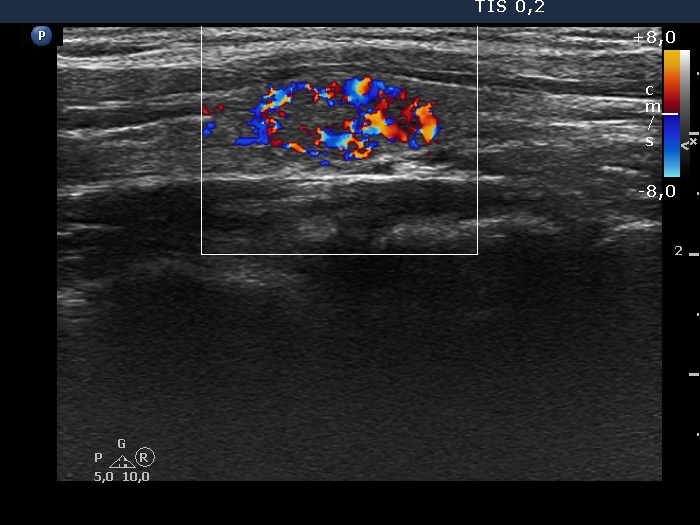

Halo sign and vascular pattern of nodules - case 2249

Follow-up investigation 3 years later (ultrasonographic picture 6)

Left lobe, longitudinal scan, color Doppler mode. The vascularization has substantially changed compared with the previous examination. It is evident that the intranodular vascularization, which was not present at the first visit, has become extremely increased. Although vascularization can be observed at the periphery of the nodule, these vessels belong to the intranodular parts of the nodule.